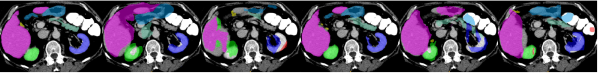

IV-I Evaluation Results on BTCV

The proposed MRE-Net achieved competitive performance on the MRBrainS18 dataset. To validate the capability of the MRE-Net to generalize for data of other modalities as well as other parts of the body, we also apply it to the BTCV dataset. However, low-shot multi-organ segmentation in abdominal CT is more challenging, mainly for two reasons: (i) the contrast of soft tissues in CT is not as good as that in MRI; and (ii) the inter-subject variations in both appearance and structure—such as shape, size, and location—can be much larger in abdominal CT than in brain MRI. From the preceding experiment on the MRBrainS18 dataset, we have learned that the data augmentation generally works for the U-Net but not for our MRE-Net. Hence, we only experiment with the corresponding settings on the BTCV dataset. The evaluation results are presented in Table VIII. As we can see, our MRE-Net-1 achieved the best performances for all organ-wise and cross-organ evaluation metrics with large margins, substantially outperforming other competing methods including U-Net-6. It is worth noting that neither ANTs nor the U-Net managed to produce reasonable results for this challenging task. On the contrary, our framework was able to overcome the large inter-subject variations using only one sample for training. To further evaluate the performance of MRE-Net-1 when compared to the U-Net trained with even more data, we train the U-Net with all the 20 scans not selected for the low-shot experiment and test it on the selected seven scans. Results showed that U-Net-20 outperformed U-Net-6 in both mean Dice and HD95, as expected; however, our MRE-Net-1 actually performed even better than U-Net-20. We conjecture that the relatively small improvements of U-Net-20 over U-Net-6 might be partially attributed to the difficulty of the problem itself, and the possibility that these 20 scans did not present enough diversity for well training of the U-Net, which was not tailored for learning with limited data. These results demonstrate superiority of our proposed MRE-Net in dealing with low-shot segmentation of data with higher extents of inter-subject variations. Fig. 4 shows example segmentations produced by the different methods in Table VIII.